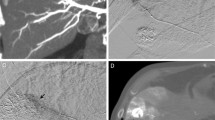

The overall image quality of MIP images was scored to be excellent in 29 (80.6%) of 36 patients, good in 5 (13.9%), and fair in 2 (5.6%), while the overall image quality of VR images was excellent in 15 (41.7%), good in 18 (50%), and fair in 3 (8.3%) (Table 1). The mean rating scores for the overall image quality were 3.75 ± 0.55 (mean ± SD) for MIP images and 3.33 ± 0.63 for VR images (p < 0.001; Wilcoxon signed rank test). In 34 (94.4%) patients the subsegmental branches of the hepatic artery were sufficiently visualized on MIP images. None of the examinations revealed artifacts that resulted in a nondiagnostic study. Moderate artifacts due to identifiable cardiac motion, which interfered with the image quality in visualization of the subsegmental hepatic artery branches, were observed on the left lateral lobe in two (5.6%) patients each for both MIP and VR images (Fig. 1). There were minimal artifacts, associated with misregistration due to respiratory motion, in 10 (27.8%) for MIP and 3 (8.3%) for VR images. All these artifacts were present on the diaphragmatic surface (Fig. 2).

Images in a 71-year-old woman with hepatocellular carcinoma. MIP image from the inferior and right anterior oblique view obtained with contrast material injection in the selective common hepatic artery. An artifact due to identifiable cardiac motion interferes with the diagnostic quality of the hepatic artery in the left lateral lobe (arrows)

The results on visualization of tumor staining and feeding artery are summarized in Table 2. Sufficient visualization of tumor staining (score, 5–3) was obtained in 18 (60.0%) of 30 HCCs for MIP images and in 11 (37.6%) for VR images; MIP images were significantly superior to VR images (mean rating score, 2.80 ± 1.35 vs. 2.00 ± 1.08; p < 0.001) (Fig. 3). The reason for the poor or absent visualization of tumor staining was insufficient contrast enhancement of the tumors in all (12 for MIP and 19 for VR images). Sufficient visualization of feeding arteries (score, 5–3) was obtained in 28 (93.3%) of 30 HCCs on MIP images; MIP images were significantly superior to VR images (mean rating score, 3.50 ± 0.97 vs. 2.83 ± 1.12; p < 0.001). Visualization was scored as excellent in 21 (70.0%) for MIP images and in 9 (30.0%) for VR images. The reasons for poor or absent visualization of feeding arteries were insufficient contrast of the vessels in all (two HCCs for MIP and three HCCs for VR images).

Images in a 71-year-old man with hepatocellular carcinoma. (A) MIP image and (B) VR image from the left oblique view obtained with contrast material injection in the selective common hepatic artery. MIP image sufficiently reveals the tumor stain (arrowheads) and the feeding artery (arrow); however, the tumor stain was insufficiently visualized on VR image

Images in a 69-year-old woman with hepatocellular carcinoma. Anteroposterior selective common hepatic angiograms, (A) 2D DSA and (B) MIP image, show tumor staining in the liver. However, the relationship between the tumor staining and the feeding artery (arrows) is unclear. (C) The superior and right anterior oblique MIP image clearly reveals the relationship between the tumor staining (arrowheads) and the feeding artery (arrow)

Images in a 57-year-old woman with hepatocellular carcinoma. (A) Anteroposterior celiac angiogram (2D DSA) shows the tumor staining and feeding artery. However, the relationship between the feeding artery for the treatment of HCC and the other hepatic artery branches are unclear. (B) MIP image from the inferior and right anterior oblique view obtained with contrast material injection in the selective common hepatic artery clearly reveals the tumor stain (arrowheads) and the anatomic relationship between the feeding artery (arrow) and the other hepatic artery branches. For TACE, the MIP image provided the guidance for successful catheterization by visualizing the origin of hepatic branch vessels